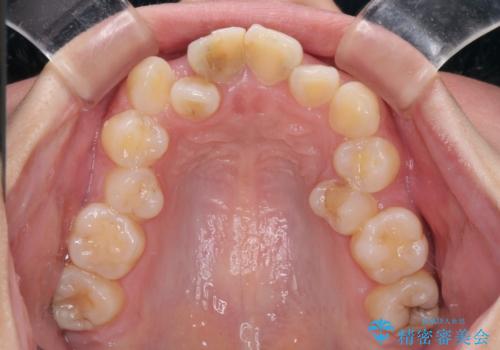

- 放置した虫歯や抜いたままの奥歯、前歯のデコボコを気にして来院された患者様です。

口元の突出感は少なく、下顎の叢生は軽微なものであったので、叢生の強い上顎左右の小臼歯を1本ずつ抜歯し、ワイヤー装置にて矯正治療を行うこととしました。

矯正治療を行う前に、根管治療の必要な上顎前歯と下顎大臼歯の根管治療を行い、矯正治療の途中で下顎の欠損部にインプラント埋入することとし、矯正治療後に補綴治療を行うこととしました。